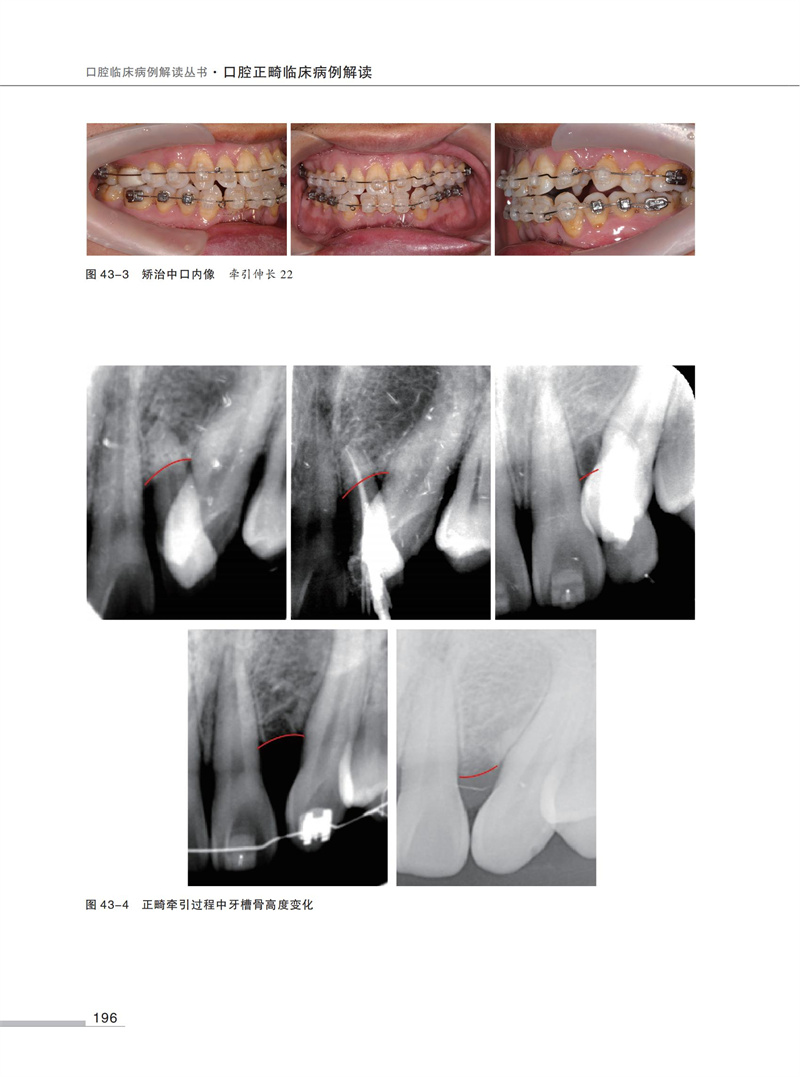

【口腔正畸臨床病例解讀】

54例正畸經典病例,每例病例均包含檢查、模型分析、診斷、治療計畫、弓絲序列、矯治結果及矯治體會等基礎資訊。

1500餘幅精美圖片,直觀清晰,易於理解。

全書共分為7部分54例病例,每部分依次討論安氏I類錯? 矯治、安氏II類錯? 矯治、安氏III類錯? 矯治、正畸-正頜矯治嚴重骨型錯? 畸形、多學科聯合矯治複雜錯? 畸形、舌側矯治、隱形矯治。 在病例的選擇中兼顧高角、低角患者,骨性、牙性問題,手術優先、普通順序的手術治療,力求盡可能全面地展示臨床上常見的病例種類和治療方法。 本書精選病例,討論全面,完整地展示出從診斷分析到治療實踐的臨床思維全過程。